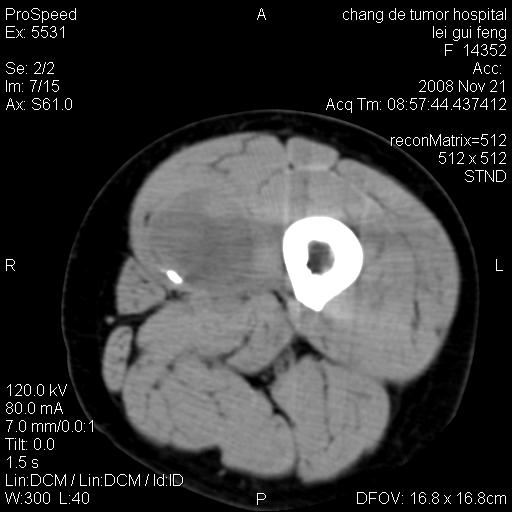

标题: CT16807:女 41 无不适 [打印本页]

标题: CT16807:女 41 无不适

考虑皮样囊肿可能性大

血管瘤可能

血管瘤

血管瘤可能性大!

黏液瘤或表皮杨囊肿

不排除横纹肌肉瘤可能。

血管瘤可能性大或畸胎瘤

考虑脂肪肉瘤

考虑血管瘤可能性大;不排除肉瘤可能。建议行活检。

脂肪肉瘤?

双是软组织肿瘤,病灶内多发钙化,另可见多量脂肪密度影,考虑畸胎瘤,血管瘤,不除外其他